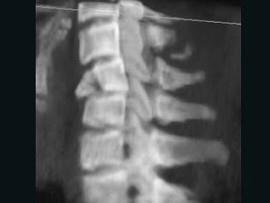

问题 男,68岁,从一两米高的平台坠落后颈部疼痛6小时,请结合影像学检查,选出最可能的诊断 ( )

选项 A、化脓性脊柱炎 B、强直性脊柱炎 C、椎体压缩性骨折 D、脊椎转移瘤 E、脊椎结核

答案 C